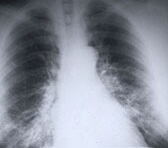

研究人员报告说,作为肺癌的二线治疗,癌症治疗药物易瑞沙与化疗作用一样。

在一个头对头的比较,kim的团队随机分配1,466名肺癌患者以前化疗的每日剂量的易瑞沙或化疗药物多西他赛每三个星期一次。

研究人员发现,两组患者的生存率大致相同。采用易瑞沙的患者的中位生存期为7.6个月,而接受多西紫杉醇的患者的中位生存期为8个月。对于具有EFGR基因突变的患者,易瑞沙的平均生存期为8.4个月,而接受多西他赛的患者的平均生存期为7.5个月。

然而,治疗组所经历的副作用存在显着差异。对于服用易瑞沙的患者,最常见的副作用是皮疹或痤疮。在接受多西紫杉醇的患者中,最常见的副作用是称为中性粒细胞减少,人格障碍和脱发的血液病症。